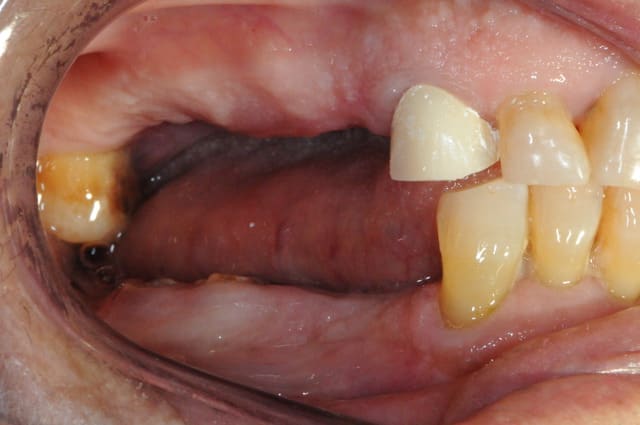

plus sérieusement mais suffisamment imparfait pour qu'on puisse trouver...

Kem inf ap neluwo - Eugenol

Kem sup2 ap bamol9 - Eugenol

pour faciliter le chmilblick : sur une arcade il y a une seule prothèse visible et sur l'autre il n'y a qu'une seule dent naturelle visible

il s'agit d'un mix de facettes et couronnes céramo-céramiques

32 et 23

bravo Henri